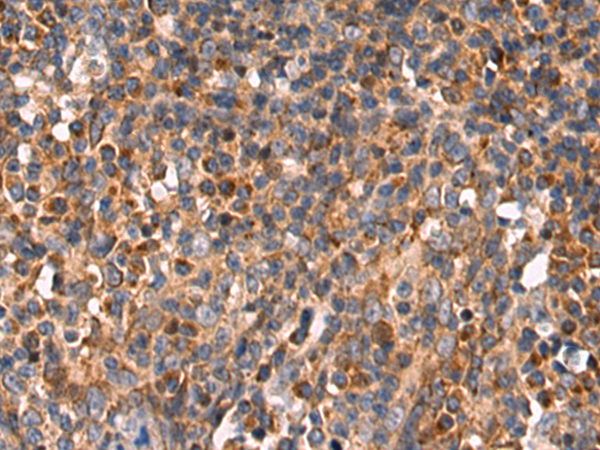

IHC positive control:

Human colorectal cancer and Human tonsil